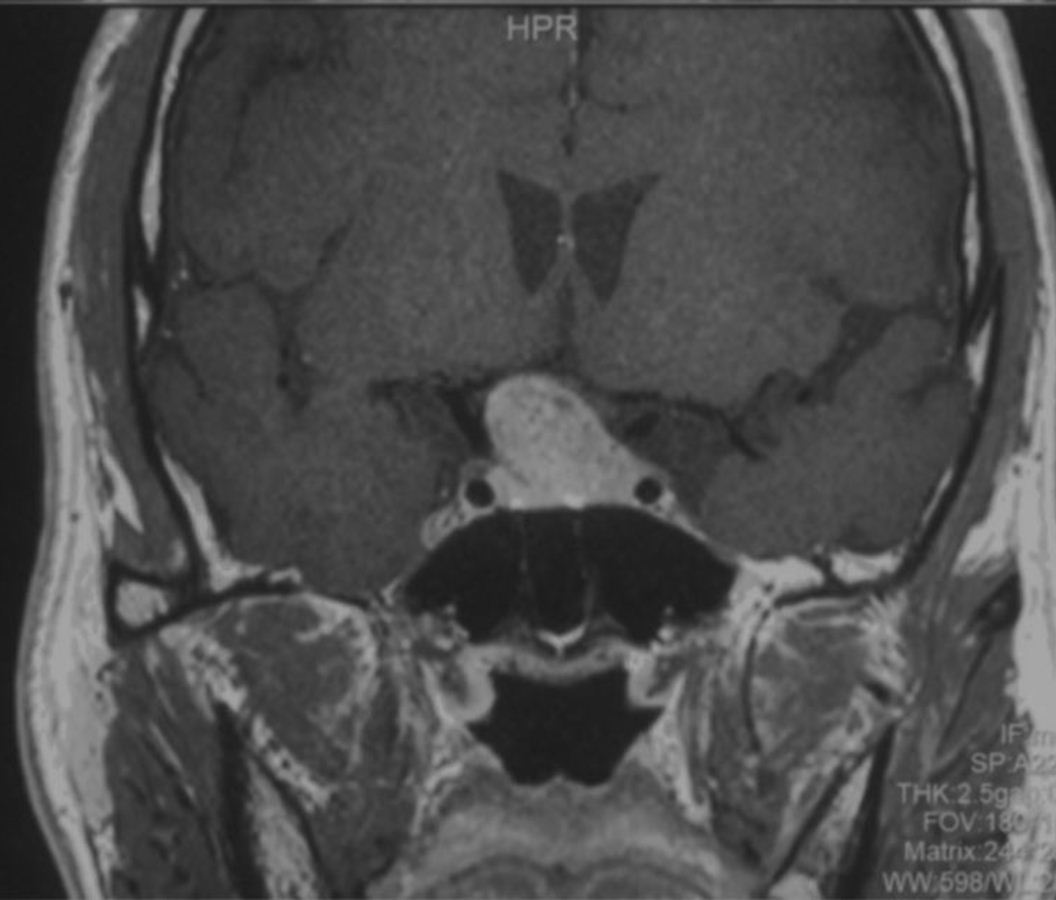

患者为中年患者,因头痛伴视物模糊半年起来就诊,鞍区增强MRI示:鞍区占位性病变,肿瘤大小约2.5cm,肿瘤突破鞍隔向上生长,顶部偏向右侧,视交叉受压明显,两侧侵犯海绵窦。T1WI为等信号,T2WI为混杂等信号,明显强化。复旦大学附属肿瘤医院神经外科高阳

术前磁共振图像: